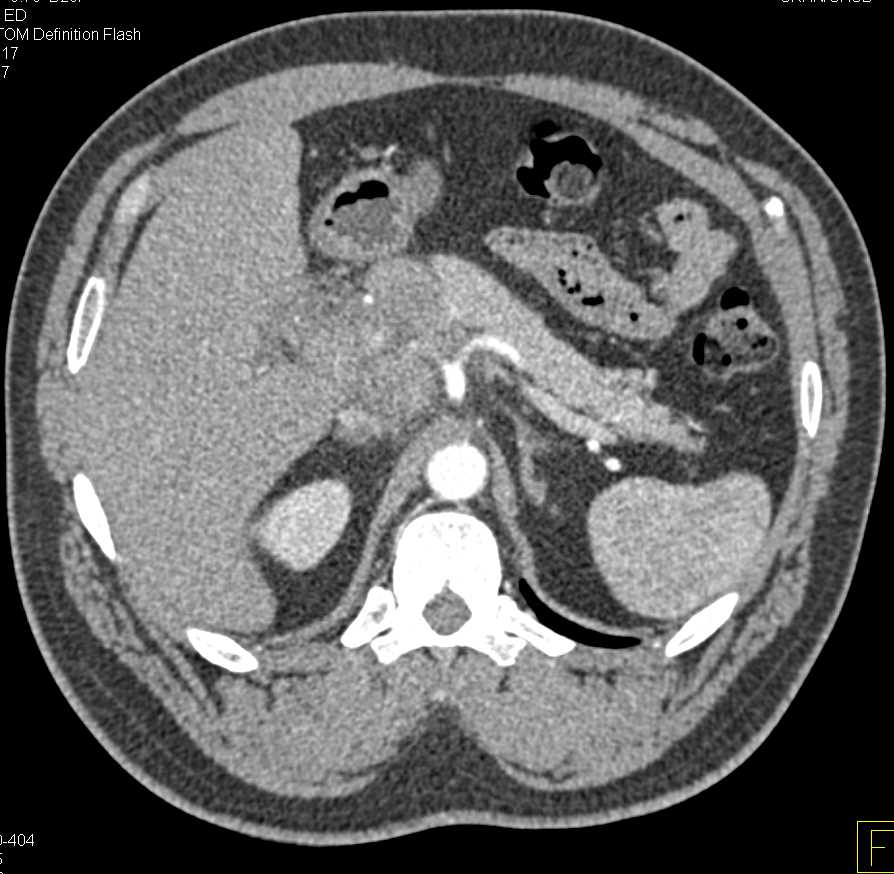

Carcinoma Body of the Pancreas